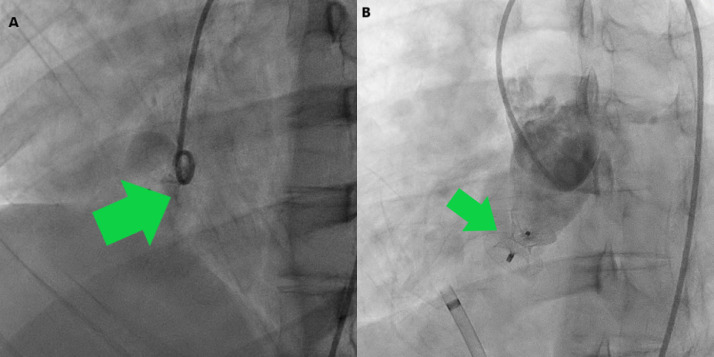

Fig. 2.

Cardiac catheterization. (A) Aortic root angiogram showing passage of dye from non-coronary sinus to right atrium. (B) 12 mm Amplatzer duct occluder II device occluding the ruptured sinus of Valsalva with no dye leakage.

A heart team approach was taken and despite repeated and detailed counselling by a board consisting of 2 consultant cardiologists, 2 consultant cardiac surgeons, and 2 consultant microbiologists regarding the utmost importance of urgent surgical approach the patient and his relatives refused to undergo surgical intervention [5]. Thus, with the consensus of all the board members an alternative treatment plan was chalked out and the patient was put on intravenous ceftriaxone 2 g OD and gentamicin 3 mg/kg/day OD. After obtaining the blood culture report we started intravenous vancomycin 2 g/day in twice divided doses over 6 weeks. The patient became afebrile within 10 days. Throughout the duration he received furosemide, metoprolol succinate, and ramipril. Regular clinical examinations were undertaken to rule out any embolic manifestations. We weekly followed up the vegetation size by transthoracic echocardiography. When there was no apparent visible vegetation after 6 weeks of antibiotic therapy and blood cultures were negative, we proceeded with computed tomography (CT) of the aorta (Online Fig. 3) to clearly delineate the anatomy, which revealed 9.1 mm RSOV with normal coronary arteries and absence of residual vegetation. After final discussion and consensus in the heart team, device closure of the anatomical defect by the antegrade approach was performed (Fig. 2 and Video 2). A 12-mm size Amplatzer Duct Occluder (ADO) II was used (Fig. 3) after the size was confirmed from echocardiography, CT, and catheterization images and videos. The procedure was uneventful and done under fluoroscopy as well as transthoracic echocardiography with Doppler imaging guidance. During the procedure we were vigilant enough to include the entire windsock but not to impinge the aortic leaflets. Echocardiography after 24 hours of the procedure confirmed the well-placed device (Fig. 3). The patient became symptom-free in the immediate post-operative period and was discharged with tablet aspirin 75 mg for 6 months. Following the current European Society of Cardiology (ESC) guidelines on IE, the patient was advised regarding endocarditis prophylaxis for the first 6 months (until expected endothelialization of the device) after the procedure with 2 g oral or intravenous amoxicillin if he underwent at-risk procedures such as dental procedures requiring intervention of the gingival or periapical region of teeth or perforation of the oral mucosa. Clinical and echocardiographic follow up has been uneventful for 6 months.